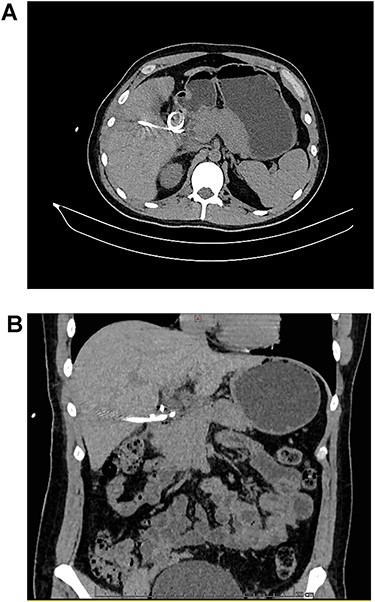

A: CT, the catheter tip can be seen lodged in the duodenal lumen. B: CT, the catheter perforates the duodenal wall.

The patient is a 29-year-old male, without past medical history. He was admitted to a private clinic due to acute cholecystitis 1 month prior. After said surgery, he was discharged on his second postoperative day without any apparent complications. Nonetheless, eight days after surgery, he experienced high fever and diffuse abdominal pain, and presented back to said clinic. A contrast-enhanced computed tomography (CT) revealed a low-density intra-abdominal collection of 105 cc (density = 25 Hounsfield Units) filled with gas. Broad-spectrum antibiotics were initiated and percutaneous drainage of the intra-abdominal collection was decided. A CT-guided percutaneous drainage was completed using a 12 French pigtail catheter, from which 100 cc of purulent fluid was recovered. A multisensitive Escherichia coli isolate was cultured from the sample. During the following five days after the drainage procedure, the output of the drain remained low and serous (15–20 mL/day). Nonetheless, on the sixth day after the procedure, the output increased (300–400 mL) and the fluid became bilious. Intestinal or biliary fistulas were among the differentials, and a new CT was planned. However, the patient requested his discharge against medical advice (due to the increasing costs associated with the treatment) and presented to our hospital, a publicly funded institution, 12 hours later. On arrival, the patient was asymptomatic, reported no changes in bowel functions or discomfort while eating and presented no febrile episodes. His clinical examination was unremarkable and the catheter drained bilious content (Fig. 1). Complementary exams including a complete blood count revealed normal leukocytes (7.5 × 109) without neutrophilia (45%), and electrolytes were also under normal, expected ranges. Thus, a new contrast-enhanced CT revealed that the pigtail catheter perforated the lateral wall of the second portion of the duodenum, with its tip lodging inside the intestinal lumen (Fig. 2A and B).